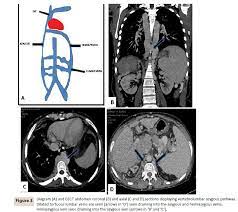

Chiasmata -mə-tə or chiasmas also chiasms 1. Esophageal varices are extremely dilated sub-mucosal veins in the lower third of the esophagus. Located in metro Denver northern Colorado and western Nebraska serving all of the Front Range our team consists of board-certified and fellowship-trained interventional radiologists. This results in hepatic congestion similar to Budd-Chiari syndrome and post-sinusoidal portal hypertension. The patients condition should be monitored throughout the procedure. They are most often a consequence of portal hypertension commonly due to cirrhosis. Toxic injury to liver sinusoids causes sloughing of endothelial cells that embolize to hepatic venules and cause eventual fibrosis of the venules. Coin in the Esophagus. There is no clear consensus regarding the number of occluded veins some authors claim that there should be at least one occluded hepatic vein 7 others state that there are no significant.